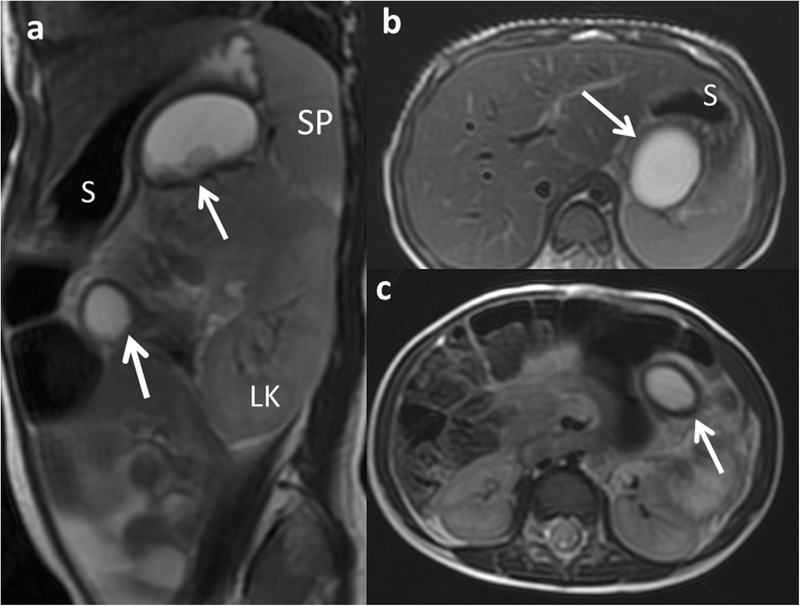

Nang ruột đôi là một tình trạng bẩm sinh hiếm gặp và xảy ra ở trẻ nhỏ, sơ sinh trong đó hệ tiêu hóa bao gồm dạ dày, ruột non, hoặc ruột già xuất hiện dưới dạ dày. Nang ruột đôi có thể gây ra nhiều vấn đề khác nhau tùy thuộc vào vị trí và kích thước của nó. Một số trường hợp nang ruột đôi có thể không gây nguy hiểm và không đòi hỏi can thiệp y tế, trong khi những trường hợp nang ruột đôi lớn hơn hoặc nằm ở các vị trí quan trọng có thể gây ra vấn đề về sức khỏe.

Tình trạng nang ruột đôi, hoặc bệnh đường tiêu hóa đôi, là một hiện tượng có thể xuất hiện ở bất kỳ phần nào của hệ tiêu hóa, từ miệng cho đến hậu môn, và có thể xảy ra ở mọi độ tuổi. Tuy tần suất bệnh này khá hiếm (chỉ xảy ra khoảng 1 trường hợp trên 4500 người), nhưng khi xảy ra, nó có thể mang đến nhiều biểu hiện khác nhau tùy thuộc vào vị trí và kích thước của đường tiêu hóa đôi.

Về phân loại, khoảng 2/3 trường hợp mắc nang ruột đôi nằm ở khoang bụng và hơn một nửa thuộc phân đoạn hỗng-hồi tràng. Những vị trí bị ảnh hưởng khác: